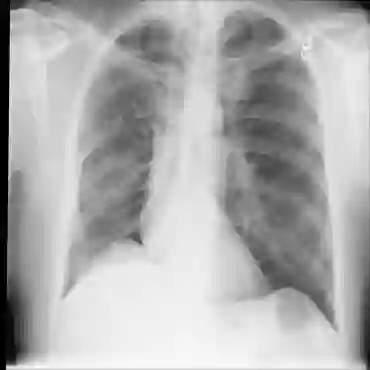

The availability of large public datasets and the increased amount of computing power have shifted the interest of the medical community to high-performance algorithms. However, little attention is paid to the quality of the data and their annotations. High performance on benchmark datasets may be reported without considering possible shortcuts or artifacts in the data, besides, models are not tested on subpopulation groups. With this work, we aim to raise awareness about shortcuts problems. We validate previous findings, and present a case study on chest X-rays using two publicly available datasets. We share annotations for a subset of pneumothorax images with drains. We conclude with general recommendations for medical image classification.